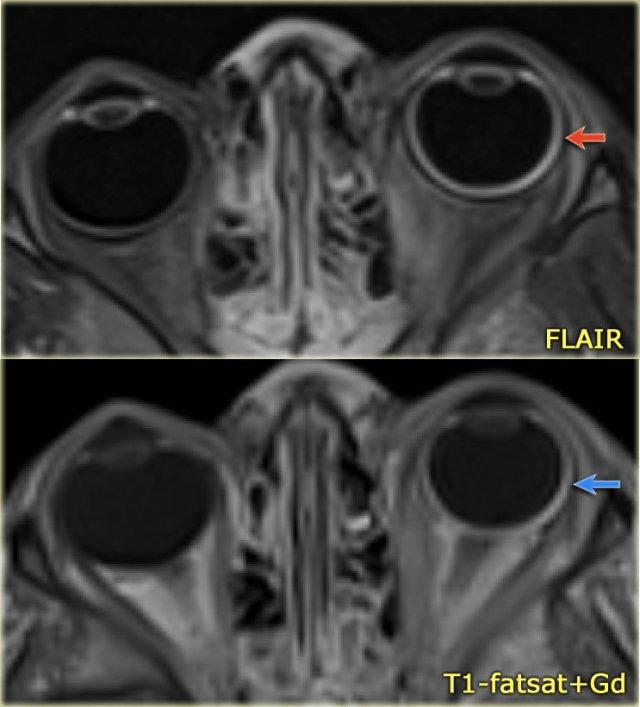

Trong hội chứng Sturge-Weber, dị dạng mạch máu của hắc mạc mắt thường được ghi nhận.

Các bệnh nhân này biểu hiện chứng buphthalmos (mắt to) do tăng nhãn áp và mù nửa thị trường.

Bất thường mắt ở bé trai 4 tuổi mắc hội chứng Sturge-Weber.

Lưu ý hình ảnh tăng tín hiệu FLAIR (mũi tên đỏ) và ngấm thuốc quá mức ở thành nhãn cầu trái (mũi tên xanh), phù hợp với u mạch hắc mạc lan tỏa.